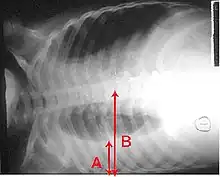

A pleural effusion appears as an area of whiteness on a standard posteroanterior chest X-ray.[12] Normally, the space between the visceral pleura and the parietal pleura cannot be seen. A pleural effusion infiltrates the space between these layers. Because the pleural effusion has a density similar to water, it can be seen on radiographs. Since the effusion has greater density than the rest of the lung, it gravitates towards the lower portions of the pleural cavity. The pleural effusion behaves according to basic fluid dynamics, conforming to the shape of pleural space, which is determined by the lung and chest wall. If the pleural space contains both air and fluid, then an air-fluid level that is horizontal will be present, instead of conforming to the lung space.[13] Chest radiographs in the lateral decubitus position (with the patient lying on the side of the pleural effusion) are more sensitive and can detect as little as 50 mL of fluid. Between 250 and 600mL of fluid must be present before upright chest X-rays can detect a pleural effusion (e.g., blunted costophrenic angles).[14]

A pleural effusion as seen on lateral upright chest x-ray- Pleural effusion as seen behind the heart.[17]